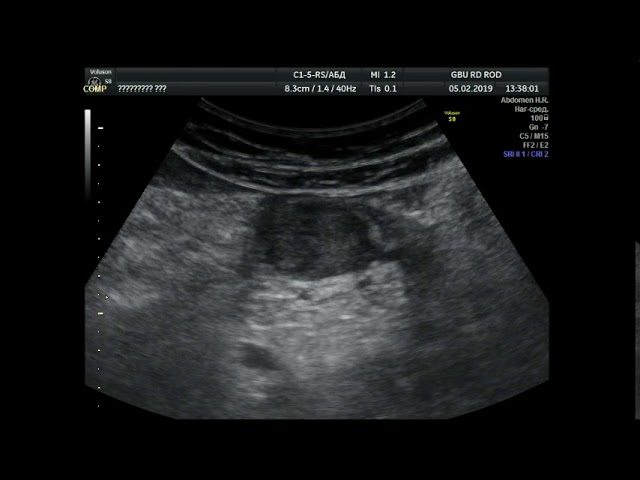

Детское УЗИ желудка/пищевода - гастроэзофагеальная рефлюксная болезнь при водно-сифонной пробеДетское УЗИ желудка/пищевода — гастроэзофагеальная рефлюксная болезнь при водно-сифонной пробе

узи желудкаузи желудка

Рак желудка на снимке УЗИ